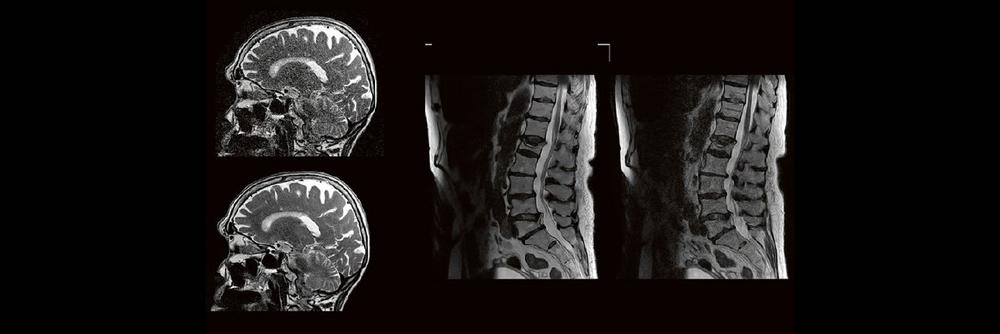

Professor Dr. med. Matthias PumbergerPD Dr. med. Torsten Diekhoff Die Dual-Energy-Computertomographie (DECT) hat für viele klinische Anwendungen bereits Einzug in die Praxis genommen. Für die Behandlung von Wirbelsäulenerkrankungen sind besonders die Darstellung von Knochenmarkveränderungen (z. B. bei osteoporotischen Frakturen) und der Bandscheibe (z. B. bei Bandscheibenvorfällen) interessant und werden intensiv beforscht. Hierdurch versprechen wir uns

Professor Dr. med. Michael Knauth Das Treffen moralischer Entscheidungen erfordert – wie jede andere Hirnleistung auch – das Zusammenwirken verschiedener Hirnareale. Der Vortrag nimmt auf eine interaktive Reise durch die Mehrzügeligkeit moralischer Entscheidungen (emotional vs. utilitaristisch) und gängiger moralischer Dilemmata (Trolley-Problem) und führt schließlich zu den mit dem Treffen dieser Entscheidungen befassten Hirnregionen und zu